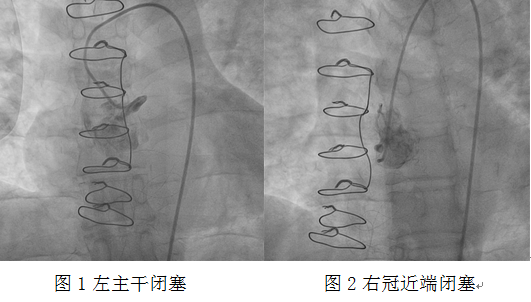

心血管介入團隊立即予患者冠狀動脈造影。造影顯示左主干閉塞、右冠狀動脈近端閉塞。此時患者表情淡漠,血氧飽和度75%,為心源性休克狀態。考慮患者為橋血管急性閉塞,如不立即開通閉塞血管,患者有生命危險!

介入團隊經過努力,發現前壁至右冠狀動脈的靜脈橋血管急性閉塞,嘗試正向開通原血管困難,此時患者血氧飽和度進一步下降,遂決定對急性閉塞的靜脈橋血管行急診介入治療。